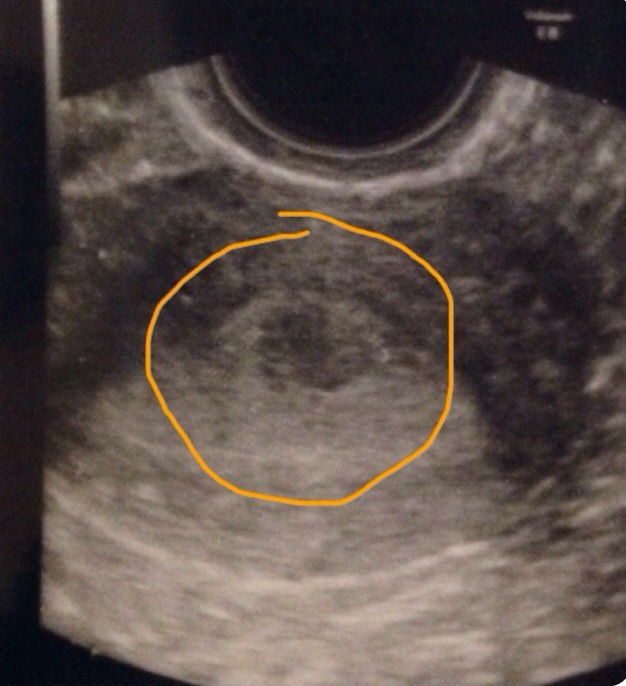

В этом цикле делаю фолликулометрию , О по УЗИ произошла 1 сентября, на 12 ДЦ. До этого была на УЗИ на 9 ДЦ, смотрели как зреют фолики, как растет эндометрий. Все было к моей радости замечательно! Это такое счастье приходить на УЗИ и слышать, что у тебя там все ок и ничего лишнего не наблюдается. В мае у меня была лапара, на которой удалили эндометриоидную кисту, делали еще и гистеру, на ней все чисто. И вот сегодня, на 21 ДЦ пришла я по назначению врача смотреть по УЗИ окно имплантации - все хорошо, ЖТ (правда кистозное) 18 мм, эндометрий 12. И какая-то фигня в матке!!! Круглое темное образование 7х8х12 мм, врач поставила миому под вопросом! Мне хочется рыдать навзрыд!!! Ну как?! Откуда?? На предыдущих УЗИ в первой фазе ничего не было( правда в этот раз я попала к другому врачу. Как такое может быть, что в первой фазе ничего не заметили, а сейчас что-то появилось?? Скоро 2 года планирования, ни одной беременности, чего я уже только не делала, а теперь еще и это... Мне плохо. Спасибо тому, кто дочитал.